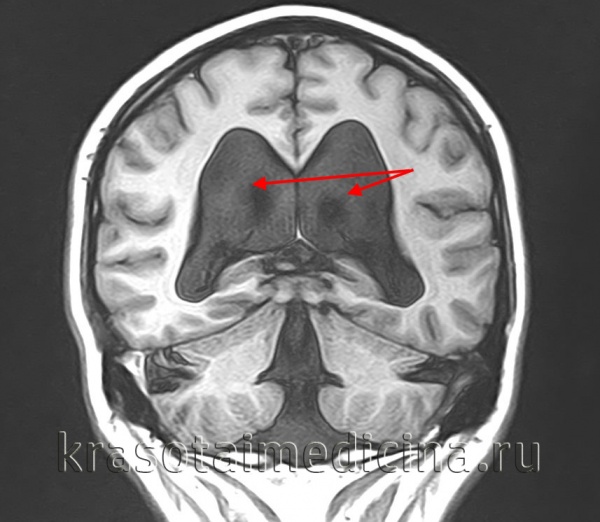

- Бивентрикулярную — увеличен объём двух боковых желудочков. Окклюзия на уровне III желудочка.

- Тривентрикулярную — расширение охватывает три желудочка. Препятствие ликворооттоку расположено в области водопровода мозга.

- Нейровизуализацию. У грудничков проводится путём нейросонографии через родничок, у остальных — при помощи МРТ головного мозга. Исследование даёт возможность диагностировать порок развития, установить локализацию ликворного блока, определить его причину. МСКТ, КТ головного мозга проводятся в сложных диагностических случаях в дополнение к МРТ, при наличии противопоказаний к МР-исследованиям.

1. Нейровизуализация: УЗИ, КТ и МРТ для оценки размеров желудочков, установления этиологии или типа гидроцефалии и исключения других патологических изменений (например, Киари, опухоли IV желудочка, тромбоза венозного синуса)

а) Острая гидроцефалия:

— Оба височных рога более 2 мм без визуализации сильвиевой или межполушарной щели

— Ширина лобного рога/бипариетальная ширина > 30%

— Трансэпендимарная абсорбция ЦСЖ.